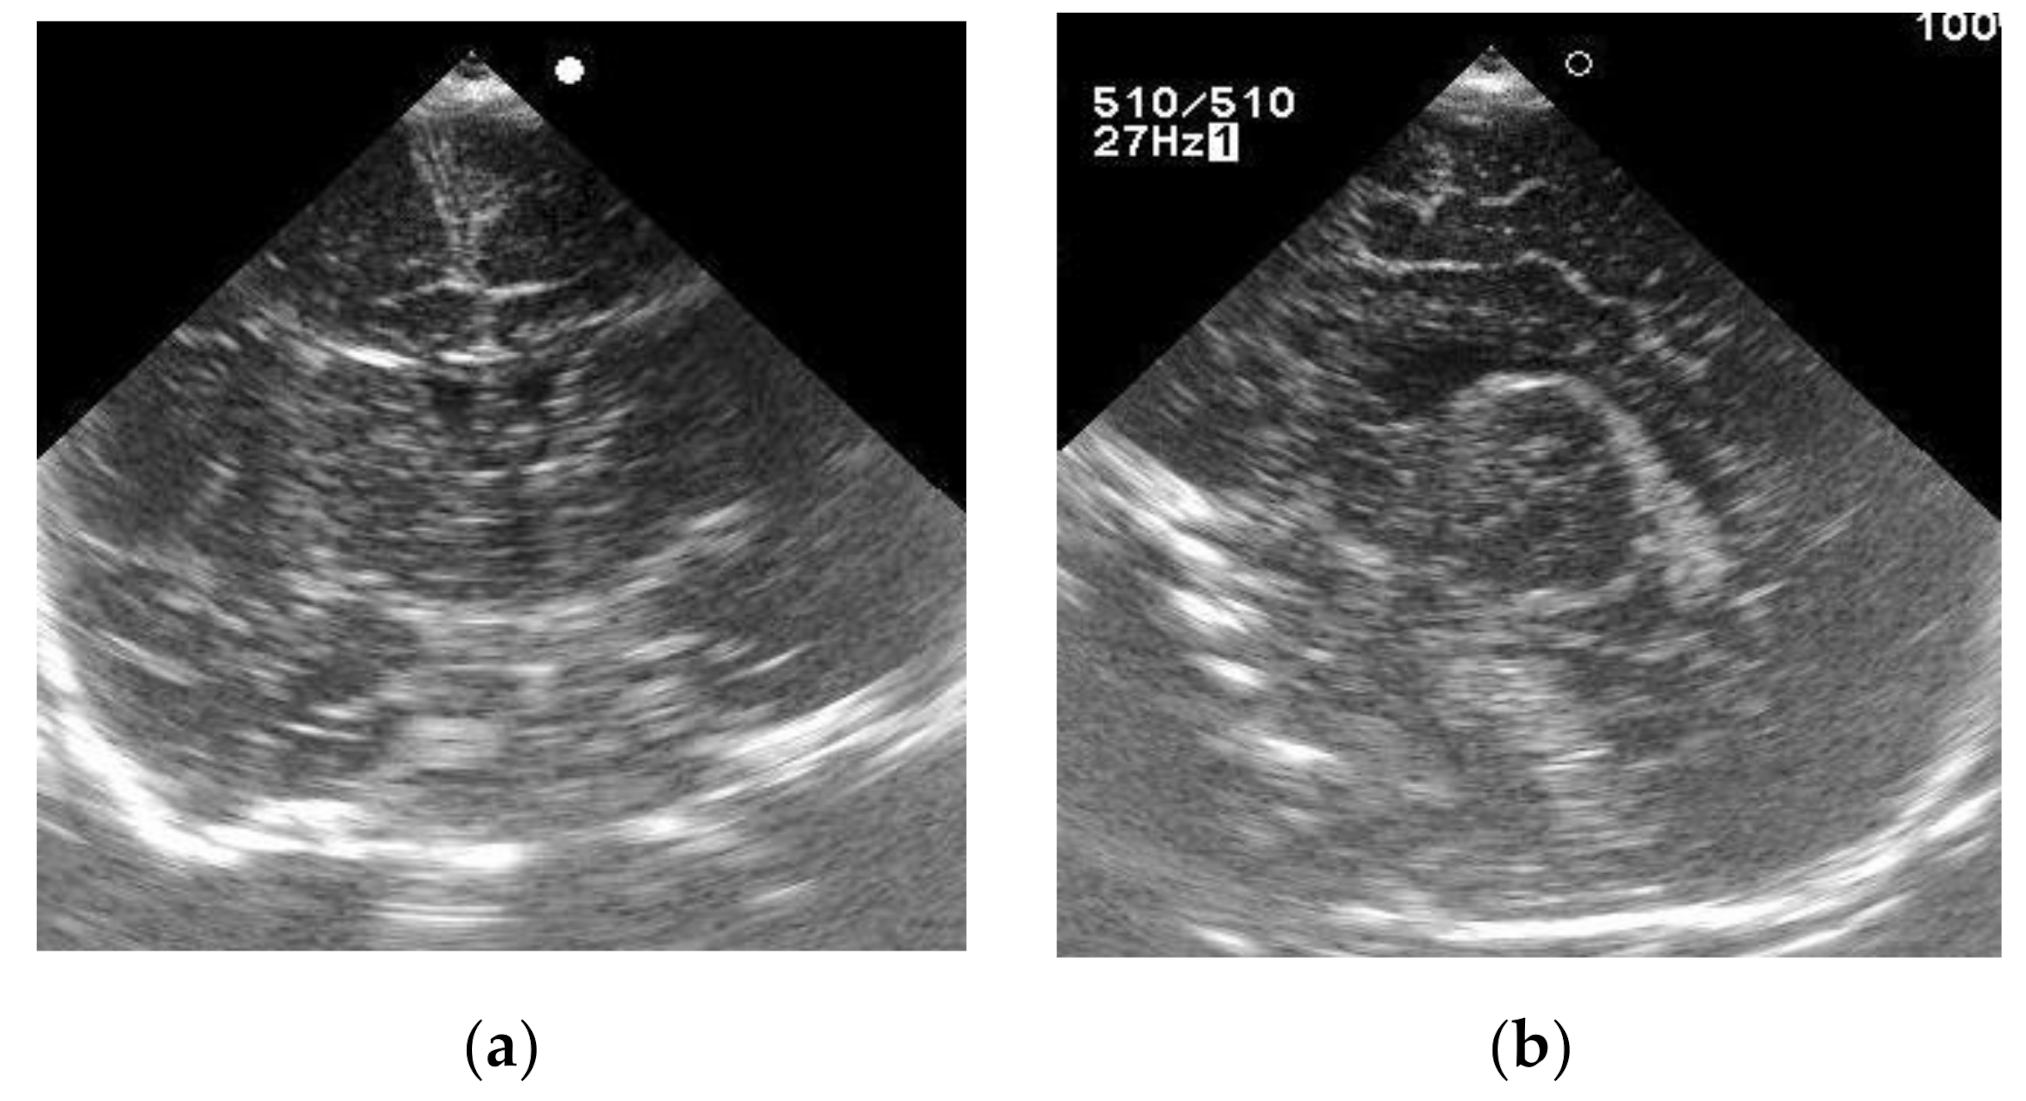

3.1. Case 1